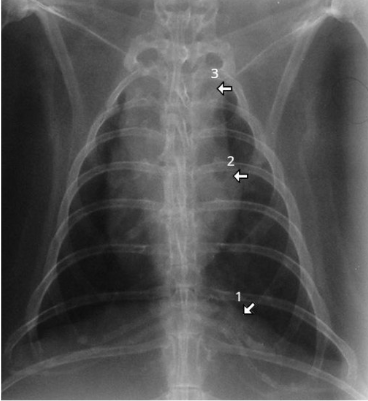

what species

what are the numbers

rabbit

2= cardiac silhouette

= trachea

where trachea bifurcates to go into different bronchi

caudal vena cava

What species and what are the numbers

1 = diaphragm 2 = cardiac silhouette

= mediastinum which is larger in rabbits